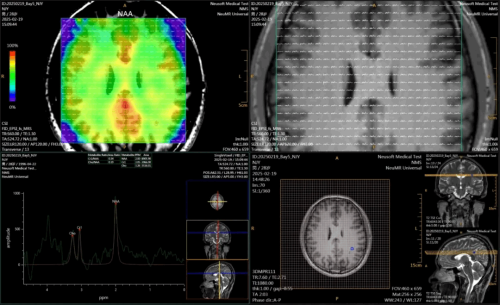

EPSI 磁共振快速回波平面谱成像

磁共振快速回波平面谱成像(Echo planar spectroscopic imaging,EPSI)技术是一种先进的磁共振波谱成像技术。其利用回波平面读出梯度的同时采集波谱和空间信息,可以实现数据的加速采集。与多体素波谱成像技术相比,EPSI具有更大的空间覆盖和更高的空间分辨率优势,可实现全脑代谢物定量分析。